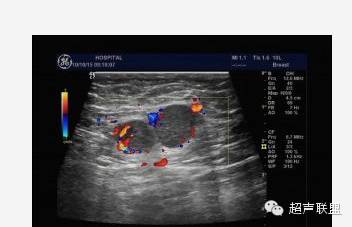

5.多普勒灵敏度和功率多普勒技术的改善,使观察乳腺内部的血管分布更为直接。在20世纪80年代初多普勒超声技术刚用于血管检测时,主要采用连续波多普勒,因为它有较高的灵敏度。乳腺肿块周围的血管内含有较高的血流速度被认为是恶性肿瘤的象征。现在,只需用彩色多普勒观察分布于肿块内外的血管数量即可作出同样的诊断。尽管对于多普勒信息的解释仍有异议,但多数研究者及ATL/FDA临床实验的结果确认了乳腺肿块中增加的血管分布预示了恶性肿瘤。

声像图表现:于右乳腺相当于六点钟,距约1.5cm处见一大小约1.0x0.6cm低回声肿物,边界尚清,形态不规,周边可检出动脉频谱样血流信号,RI为0.67,余腺体回声粗糙,未见占位性病变。右腋下另见数个淋巴结,较大的为1.4x0.8cm,边界清,周边呈低回声,中心部呈高回声。

签别诊断:主要是和乳腺Ca的签别,癌肿内还可以有“沙粒样”的微钙化灶,浆细胞性乳腺炎的病灶内血管多为低阻力型,RI一般小于0.70;乳腺癌的病灶内血管一般为高阻力型,RI多数大于0.70。(其机理是由于肿瘤血管在解剖结构上缺乏肌层,且没有一般血管从近端到远端逐渐变细的特点,导致局部受压,使血管阻力升高;而浆细胞性乳腺炎则无上述特点)。当图象上两者有交叉不好区分时,结合病史是最关键的,浆细胞性乳腺炎既往可有红、肿、热、痛的病史,急性期和亚急性期的结节有触痛,常有导管扩张,慢性期的结节可存在数年之久,抗生素治疗无效时,应想到本病的可能性;乳腺癌患者常无症状,仅触及包块,病史短,不伴导管扩张。